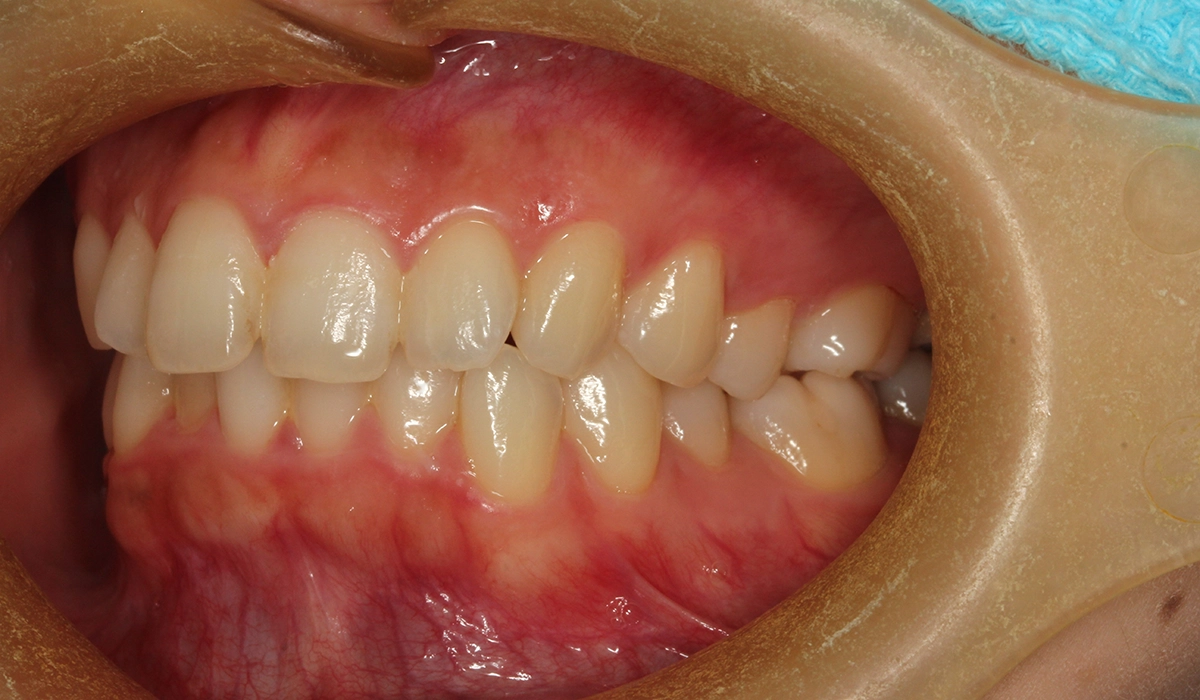

術前:右側

術後:右側